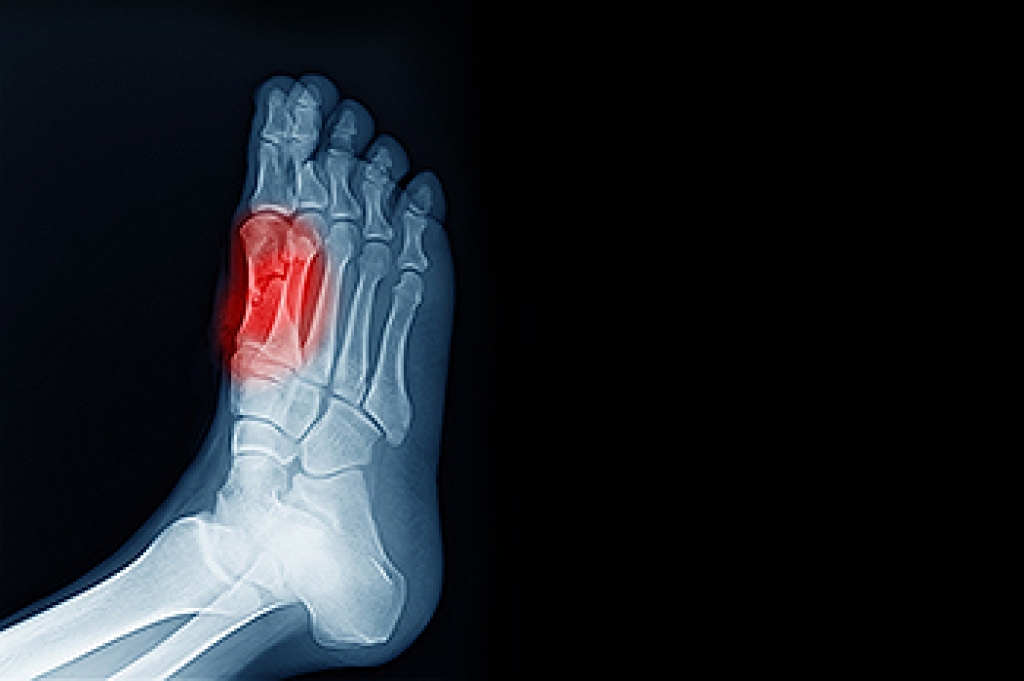

Sesamoiditis is a condition that involves inflammation of the small sesamoid bones located beneath the big toe joint. These bones help absorb pressure and assist in movement, but excessive strain can lead to irritation and pain. Common causes of sesamoiditis include repetitive stress from activities like running, dancing, and jumping, as well as wearing high heels or improper footwear. Individuals with high arches or an abnormal foot structure may also be more prone to developing this condition. Symptoms often include pain beneath the big toe, swelling, and difficulty bending or moving the toe. The discomfort may worsen with activity and improve with rest. If you have pain in this part of your foot, it is suggested that you consult a podiatrist who can accurately diagnose and treat sesamoiditis.

Sesamoiditis is a condition of the foot that affects the ball of the foot. It is more common in younger people than it is in older people. It can also occur with people who have begun a new exercise program, since their bodies are adjusting to the new physical regimen. Pain may also be caused by the inflammation of tendons surrounding the bones. It is important to seek treatment in its early stages because if you ignore the pain, this condition can lead to more serious problems such as severe irritation and bone fractures.

Causes of Sesamoiditis

Treatment for sesamoiditis is non-invasive and simple. Doctors may recommend a strict rest period where the patient forgoes most physical activity. This will help give the patient time to heal their feet through limited activity. For serious cases, it is best to speak with your doctor to determine a treatment option that will help your specific needs.